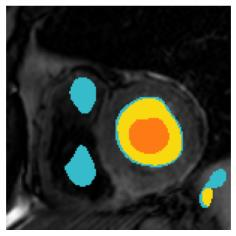

Although supervised deep-learning has achieved promising performance in medical image segmentation, many methods cannot generalize well on unseen data, limiting their real-world applicability. To address this problem, we propose a deep learning-based Bayesian framework, which jointly models image and label statistics, utilizing the domain-irrelevant contour of a medical image for segmentation. Specifically, we first decompose an image into components of contour and basis. Then, we model the expected label as a variable only related to the contour. Finally, we develop a variational Bayesian framework to infer the posterior distributions of these variables, including the contour, the basis, and the label. The framework is implemented with neural networks, thus is referred to as deep Bayesian segmentation. Results on the task of cross-sequence cardiac MRI segmentation show that our method set a new state of the art for model generalizability. Particularly, the BayeSeg model trained with LGE MRI generalized well on T2 images and outperformed other models with great margins, i.e., over 0.47 in terms of average Dice. Our code is available at https://zmiclab.github.io/projects.html.